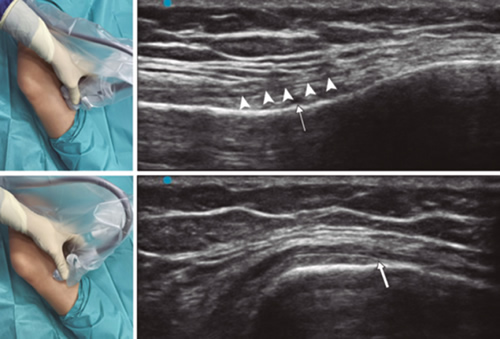

Figura 2